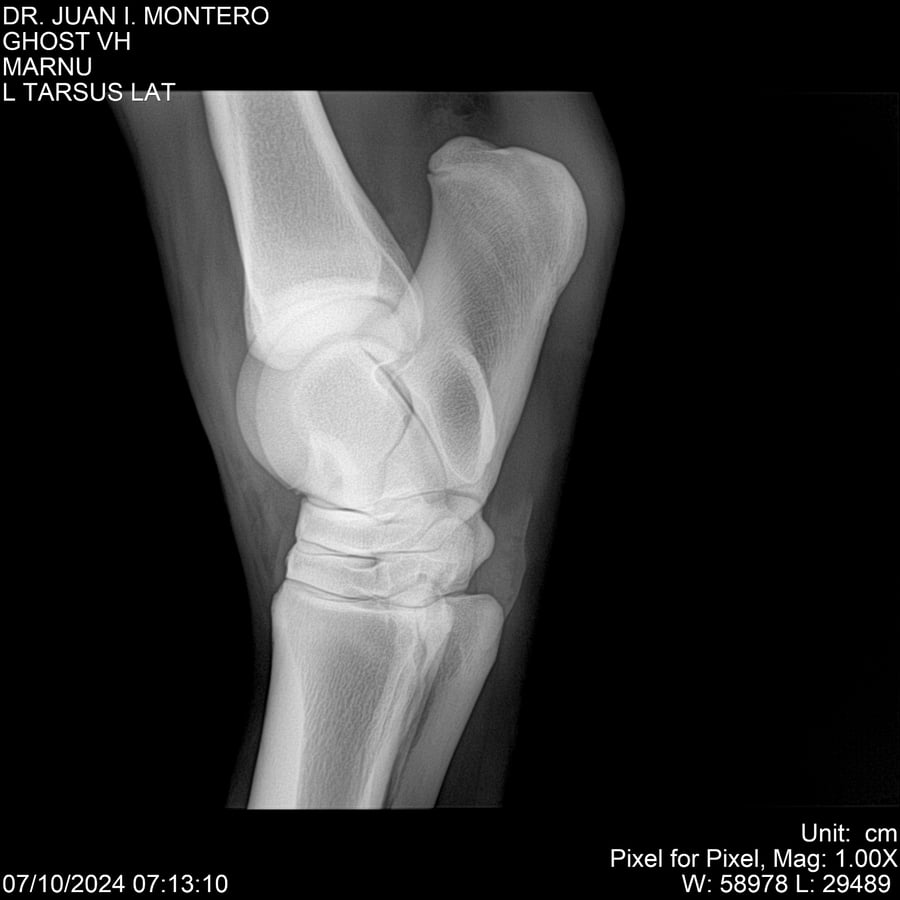

LOTE 15, GHOST VH 🔥 🔥 🔥 Lote Anterior Volver al remate Lote Siguiente Ficha Contacto Montevideo - Ficha del Lote Identificador: #282525 Categoría: Yeguarizos Montevideo - 69 Visualizaciones ClicData Contacto Empresa: Abelenda N. R., Walter Hugo Nombre*: Teléfono* : E-mail* : Mensaje Enviar Registrese gratis Este contenido Exclusivo está disponible sólo para usuarios registrados Ingresar